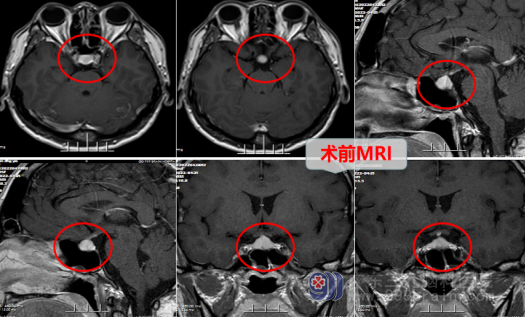

办理好住院后,外十科的医生立即给闫大哥进行了更详细的检查,头颅MR检查提示:垂体前后叶异常信号影,考虑Rathke`s囊肿可能性大。COR+GH+性激素五项:皮质醇(COR),2.2ug/L低,促肾上腺皮质激素(ACTH),<1.5ng/L,低,拿到检查结果后,外十科的专家组团队立即对闫大哥的病情展开了讨论,最后一致认为,手术是最佳的治疗方案,并且推荐采取内镜经鼻-蝶入路的方式,这种微创手术方式不用开颅,具有创伤小、恢复快的优点。

在得到家属和病人的同意之后,医生在4月28日对闫大哥实施了“内镜经鼻蝶鞍区Rathke`s囊肿切除术”。手术很成功,术后复查头部MR检查:原病灶(囊肿)已切除,已消失。病理诊断结果也的确是Rathke`s囊肿,经过术后一周的恢复,内分泌检验结果也恢复正常,闫大哥顺利康复出院了。